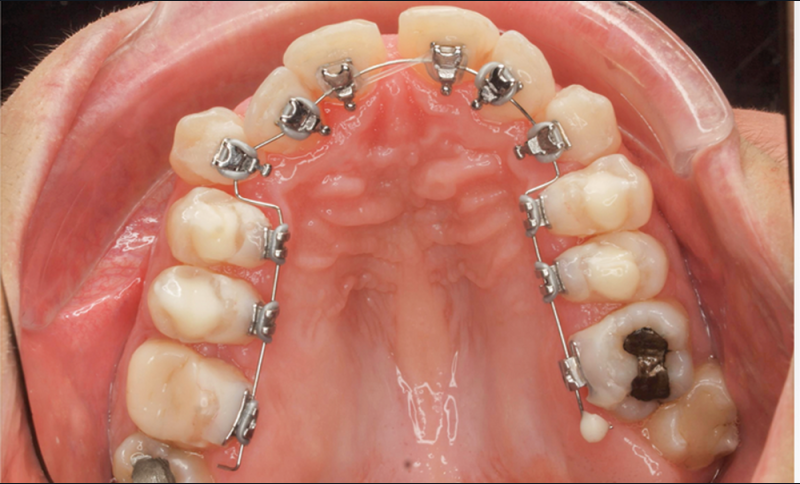

- Quatrième rendez-vous (fig. 2d) : des arcs TMA .017 x .017 sont posés. Les premières et deuxièmes molaires sont collées en vestibulaire avec un arc sectionnel NiTi 0,019×0,025.

- Cinquième rendez-vous (fig. 2e) : des arcs TMA .017 x .025 sont posés et des tubes linguaux collés sur 17 et 27 pour le port d’élastiques criss-cross nocturnes.

- Sixième rendez-vous (fig. 2f) : les cales sont déposées. Un pliage de finition sur 21 est réalisé pour améliorer son angulation.